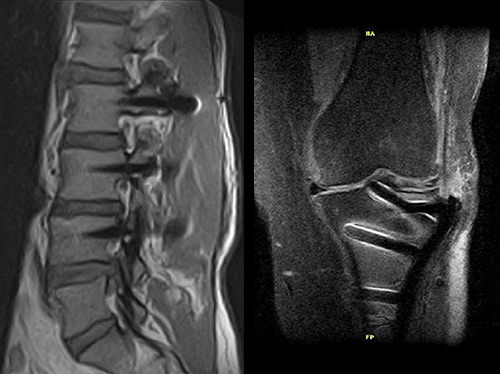

МРТ-система нового покоління з відкритим магнітом та напругою магнітного поля в 0.4 Тесла. МРТ-томограф належить то нової генерації діагностичних систем Esaote й призначений для обстеження органів і систем всього тіла.

Всі переваги і якість зображення спеціалізованих МРТ томографів Esaote для дослідження опорно-рухового апарату реалізовані в Magnifico. А на додаток, нові можливості – обстеження органів черевної порожнини, тазу та кровоносної системи.

- Висока роздільна здатність зі зрізами до 0,3 мм в ізотропному 3D зображенні;